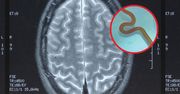

Tasiemiec - pasożyt, który zasiedla układ pokarmowy człowieka, tam rozwija się, karmi kosztem chorego i może osiągnąć długość nawet kilkunastu metrów. Tasiemiec dzieli się na uzbrojonego i nieuzbrojonego. Pasożyty przenoszą się do organizmu człowieka głównie drogą pokarmową - najczęściej w wyniku zjedzenia zakażonego mięsa. Chorobie towarzyszy utrata wagi i bóle brzucha. Tasiemce są szczególnie niebezpieczne dla życia.

Pierwszy taki przypadek na świecie. "To żyje i wije się"